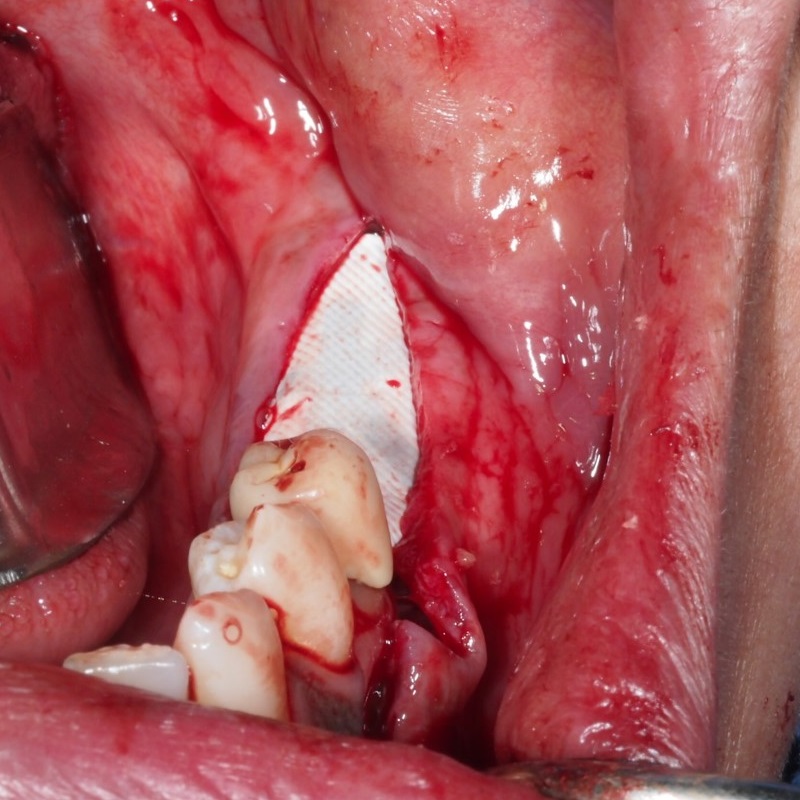

- Levantamiento de colgajo

- Preparación de lecho oseo con agujeros de decorticalización

- Colocación de membrana Jason